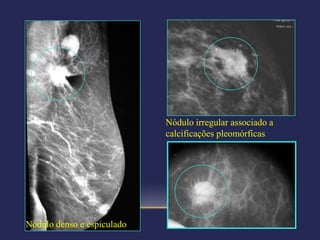

CATEGORIA 4C – SUSPEIÇÃO

MODERADA:

Nódulo sólido irregular

com limites mal

definidos.

Novo agrupamento de

calcificações

pleomórficas.

CATEGORIAS DE AVALIAÇÃO

 Categoria 5 – altamente sugestiva de malignidade –

biópsia mandatória

 Probabilidade >95% de CA

 Imagens suspeitas:

Nódulos espiculados/irregulares/de alta densidade

Calcificações finas/lineares

Nódulos espiculados/irregulares com calcificações

pleomórficas

Atlas BI-RADS (ACR) 4ª edição

Nódulo irregular associado a

calcificações pleomórficas

Nódulo denso e espiculado